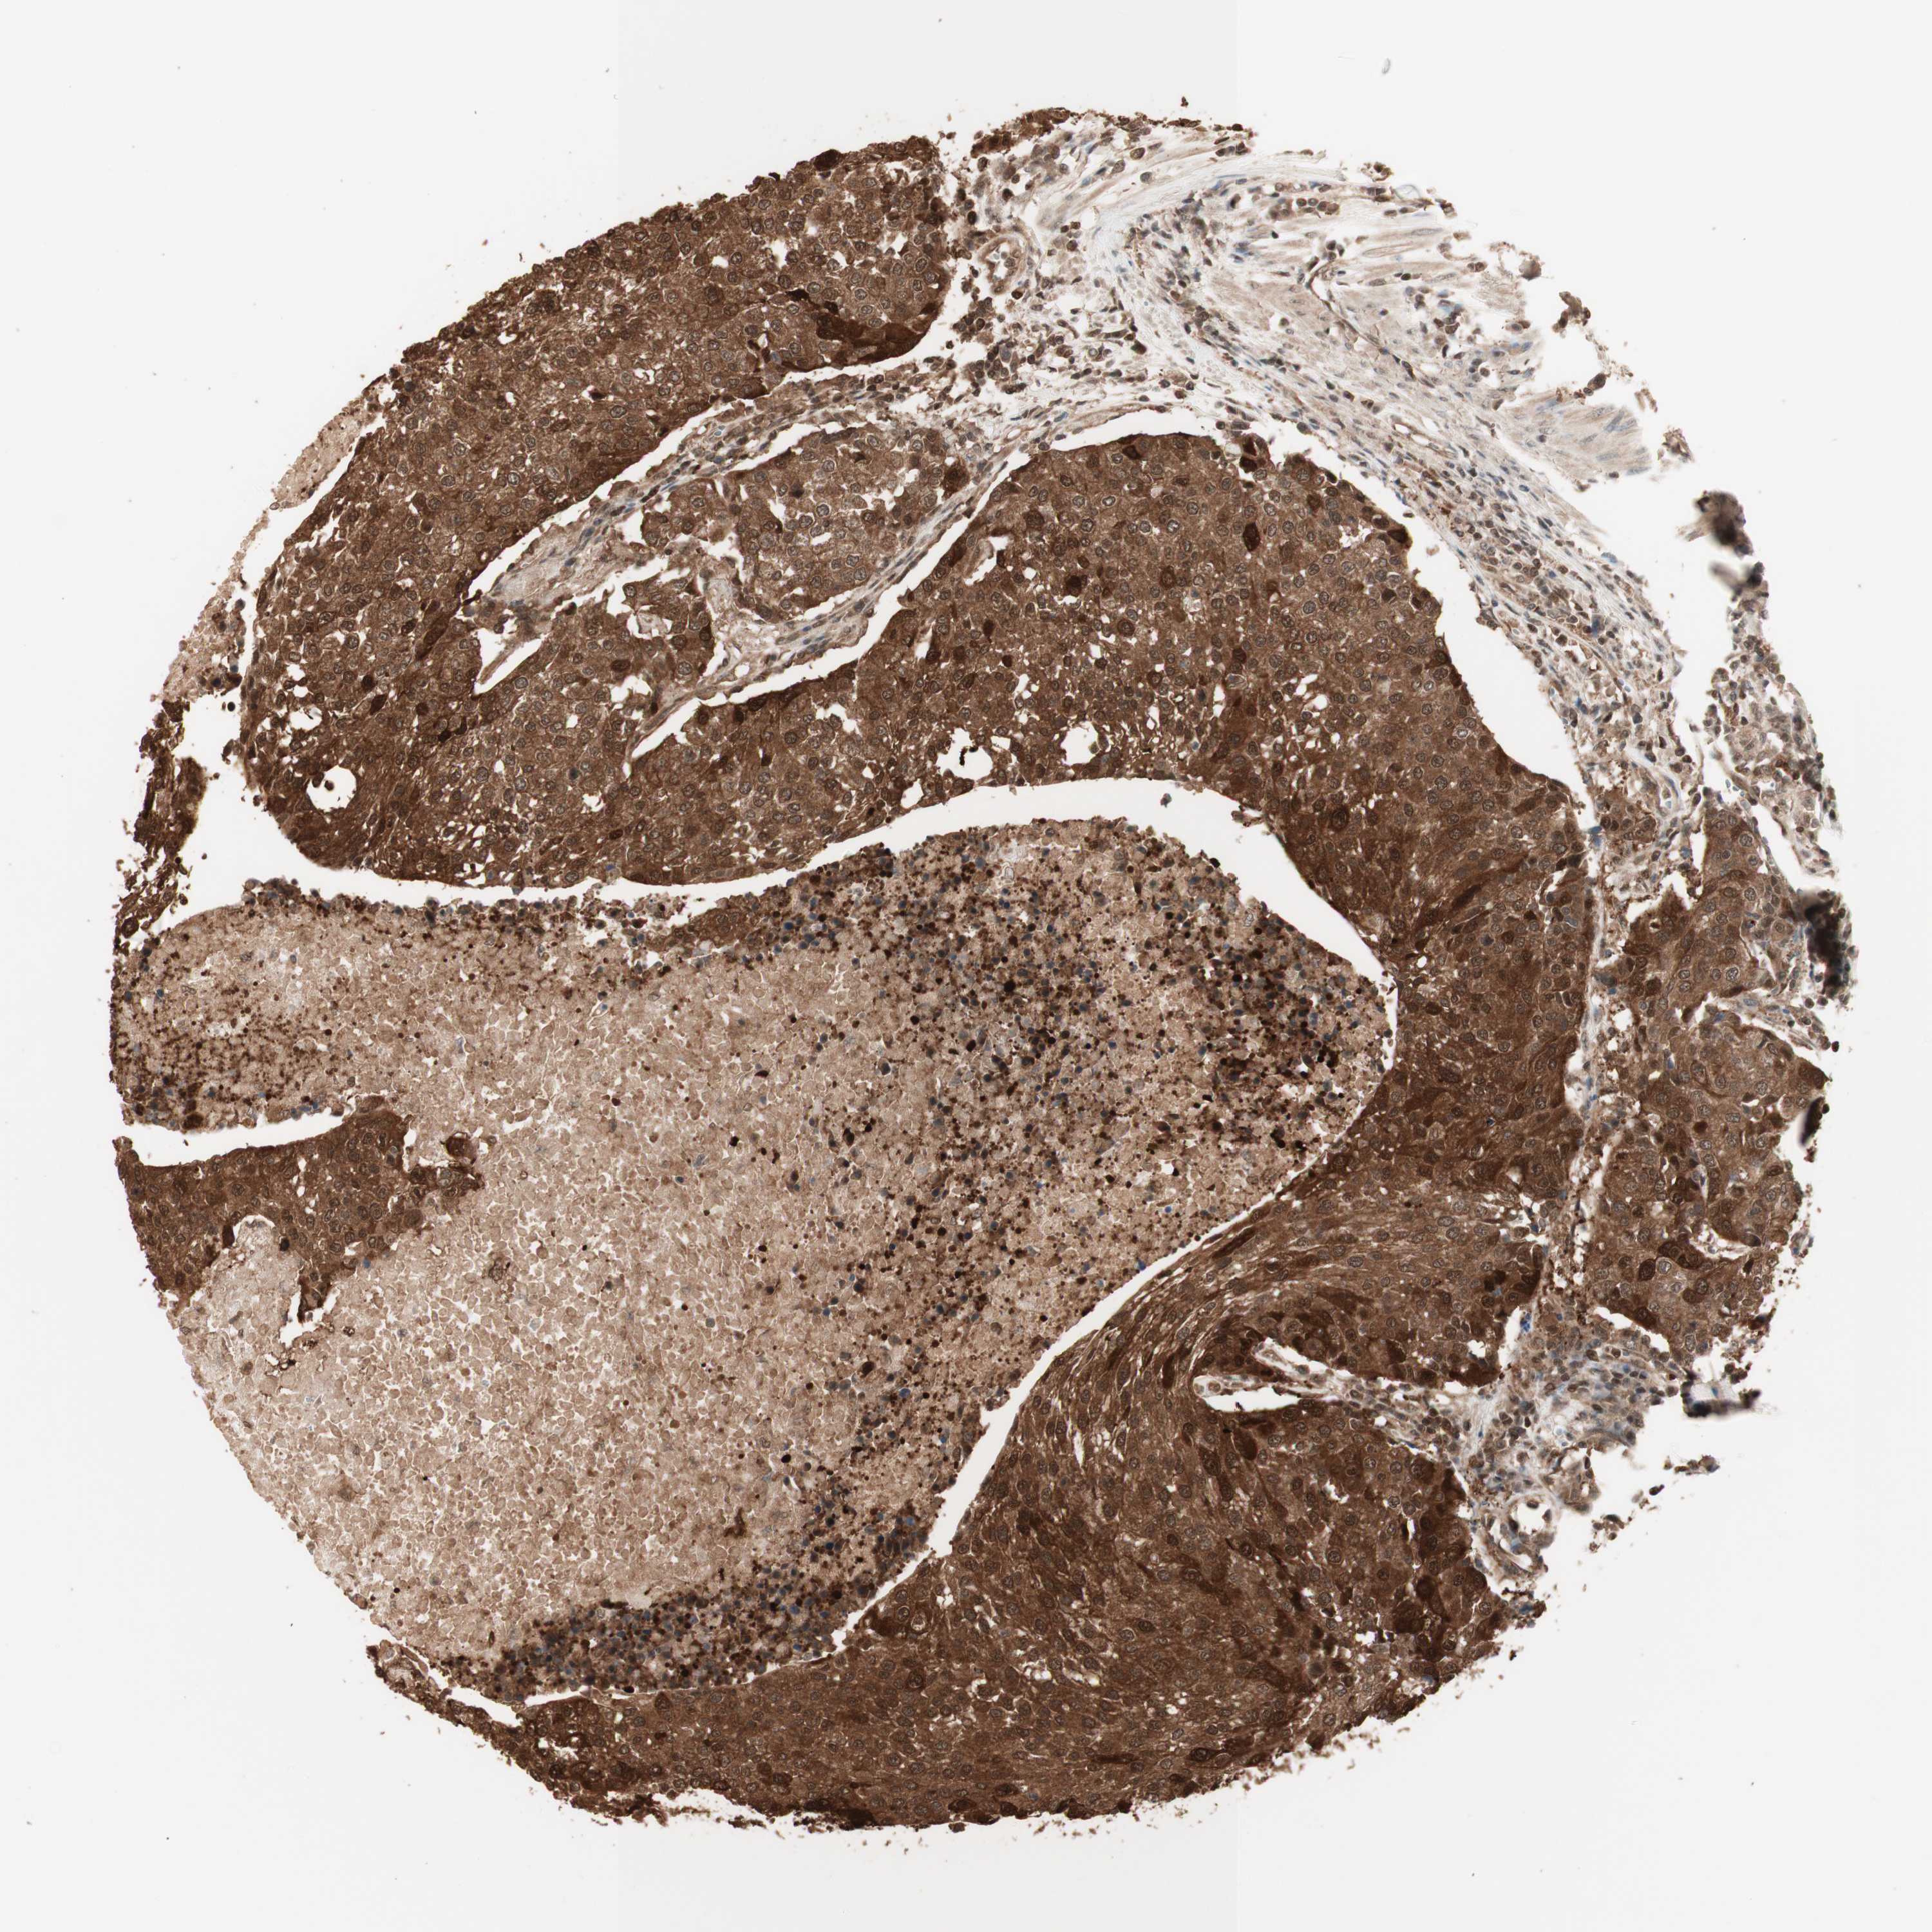

UROTHELIAL CANCER - Protein expressioni

A mouse-over function shows sample information and annotation data. Click on an image to view it in a full screen mode. Samples can be filtered based on level of antibody staining by selecting one or several of the following categories: high, medium, low and not detected. The assay and annotation is described here.

Note that samples used for immunohistochemistry by the Human Protein Atlas do not correspond to samples in the TCGA dataset.

Antibody stainingi

Antibody staining in the annotated cell types in the current human tissue is reported as not detected, low, medium, or high, based on conventional immunohistochemistry profiling in selected tissues. This score is based on the combination of the staining intensity and fraction of stained cells.

Each image is clickable and will lead to virtual microscopy that enables deeper exploration of all samples and also displays staining intensity scores, fraction scores and subcellular localization as well as patient and tissue information for each sample.

Antibody HPA007925

Antibody HPA011212

Antibody CAB003759

Antibody CAB080290

Staining

High

Medium

Low

Not detected

Intensity

Strong

Moderate

Weak

Negative

Quantity

>75%

75%-25%

<25%

None

Location

Nuclear

Cytoplasmic/membranous

Cytoplasmic/membranous,nuclear

Urothelial carcinoma, Low grade

Urothelial carcinoma, High grade